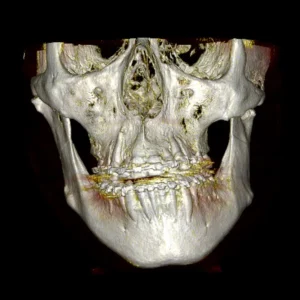

Cirugía ortognática (asimetrías faciales)

Corrección quirúrgica de deformidades óseas en mandíbula y maxilares para mejorar estética, mordida y respiración.

La cirugía ortognática, del griego orthos, «recto» y gnathos, «mandíbula», es una intervención quirúrgica que se encarga de corregir las deformidades dento-craneo-maxilofaciales mediante movimientos óseos maxilares y mandibulares, para lograr el equilibrio perfecto entre todas las características faciales del paciente.

Este tipo de alteraciones faciales aparecen en la fase de crecimiento de los pacientes, se estabilizan al final de la misma, y pueden causar problemas como apnea del sueño, trastornos de la ATM, problemas de maloclusión o falta de armonía esquelética, entre otros.